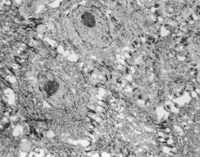

经MEBT/MEBO治疗10天,创面组织切片可见表皮棘层棘细胞出现并有桥粒连接(图5-3-14~5-3-15)。颗粒层颗粒细胞出现。在基底细胞层可见黑色素小体(图5-3-6~5-3-17)。并可见小血管周围的吞噬细胞有吞噬现象(图5-3-18),说明其功能也已经在恢复。

5-3-14 MEBT/MEBO治疗20天,4个棘细胞的桥粒连接 TEM×3500

5-3-15 桥粒结构 TEM×20000

5-3-16 颗粒细胞 TEM×3500